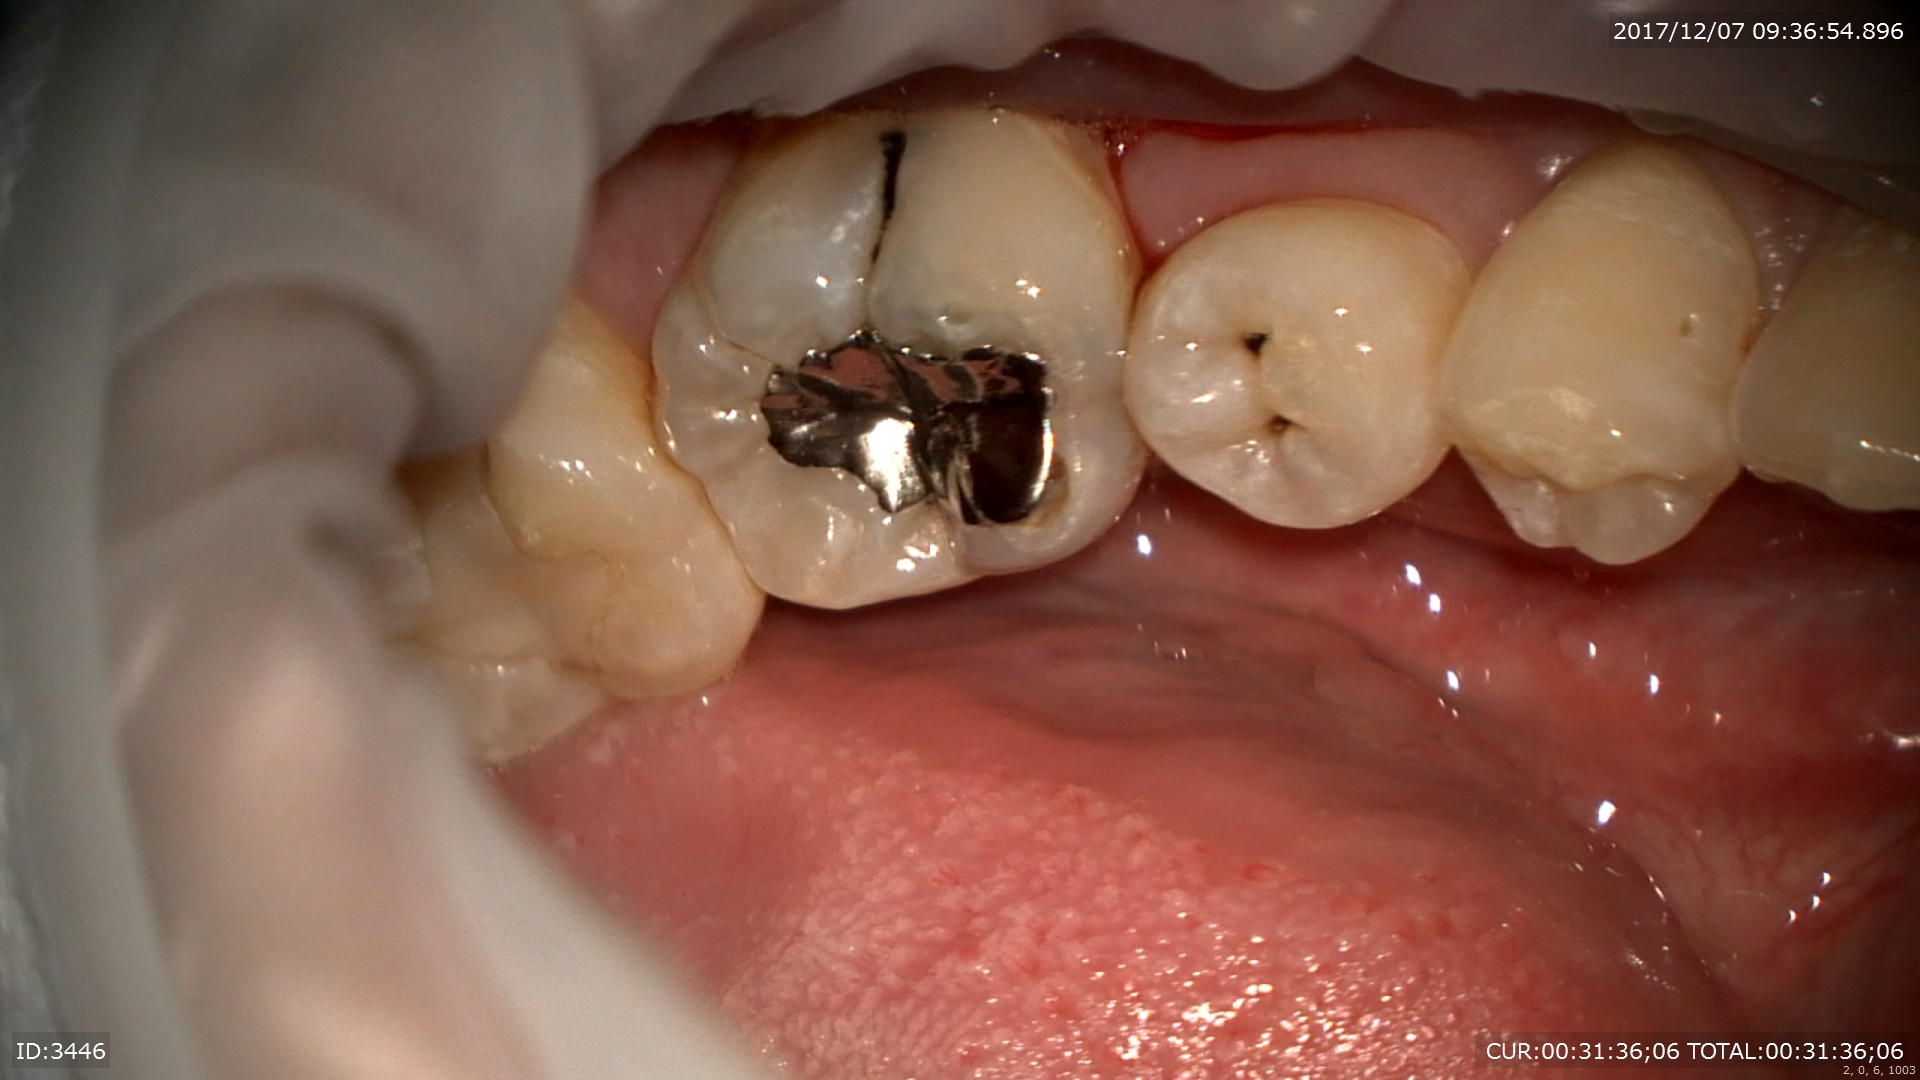

2ケース目:銀歯虫歯。私はこの銀歯治療は行いませんが、この銀歯を行わない理由がここにあります。銀歯が腐食していますね。

中は

こんな感じ